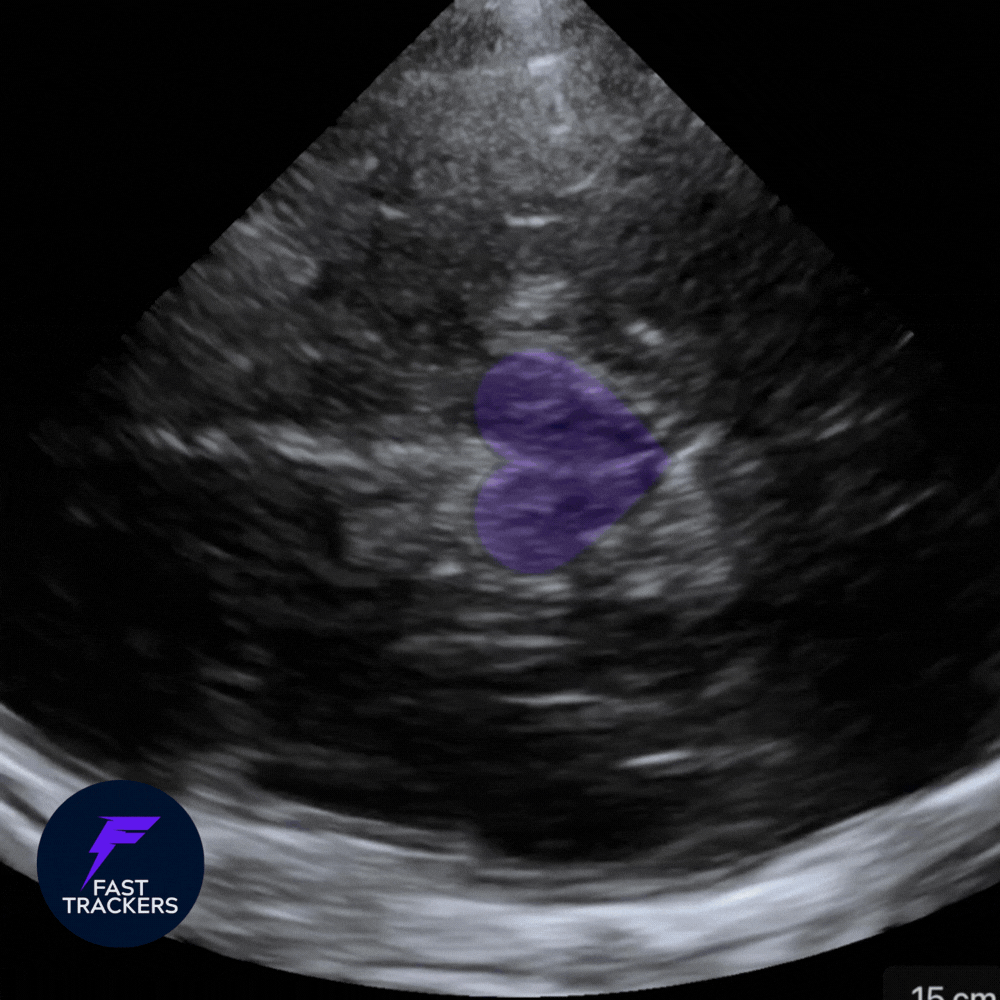

🧠 Fenêtre temporale

Region temporale, devant le pavillon de l'oreille.

Cible : Artère cérébrale moyenne (ACM)

1️⃣ Étape initiale : mode B + préréglage Doppler Transcrânien (DTC / TCI)

Toujours commencer en mode B, sans Doppler.

💡 Activer le prereglage Doppler Transcrânien (DTC / TCI) pour beneficier des calculs automatiques !

-

Fenêtre temporale.

Identifier la voûte osseuse temporale controlatérale.

Au centre : structure légèrement hypoéchogène en forme de papillon/coeur → tronc cérébral.

➡️ Le tronc cérébral est ton repère anatomique.

L’ACM chemine en antéro-latéral par rapport à lui.